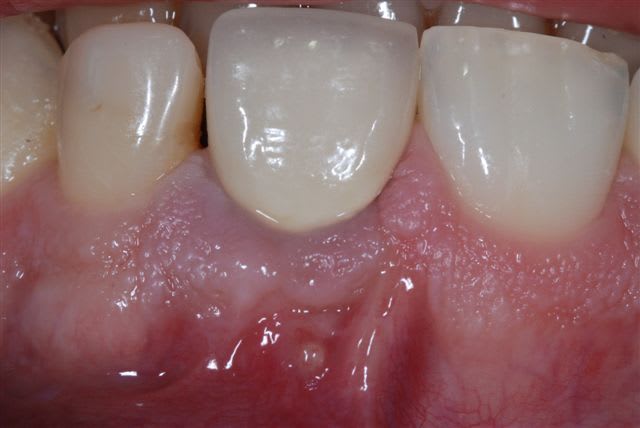

j'ai eu un cas ce matin tout indiqué pour cette technique, racine de 21 fracturée il y a 3 ans lors d'une intubation. j'ai découpé une biomend extend 15x20 en cône (maintenant zimmer commercialise des membranes déjà découpées).

Vue pr  op q3cgpn - Eugenol

Dent extr 2 yjnomm - Eugenol

Alveole kv77zk - Eugenol